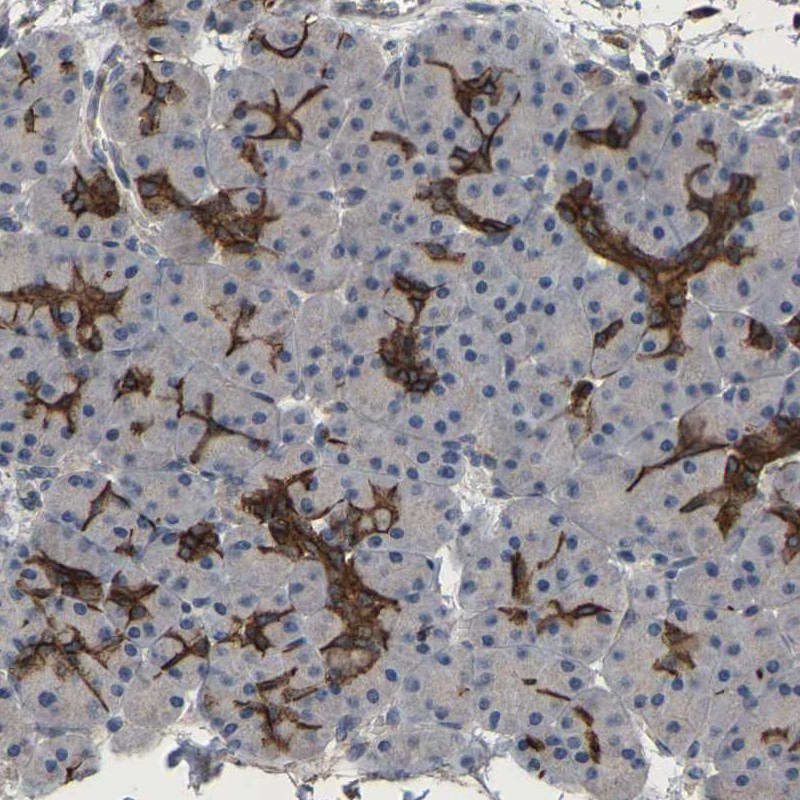

Immunohistochemical staining of human pancreas shows distinct cytoplasmic positivity in intercalated ducts.